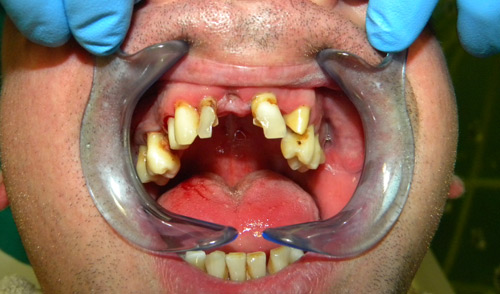

• ekstrakcije zuba

• komplikovane ekstrakcije

• Protetika, totalne proteze

• Metalokeramičke krunice (prije)

• Bezmetalna keramika (prije)